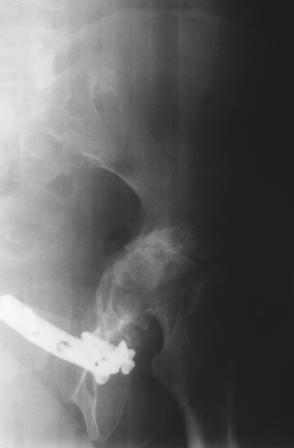

Уважаемые коллеги! Пациентка 32 года с застарелым повреждением таза, после остеосинеза лонного сочленения пластиной. Посоветуйте с выбором тактики и методик лечения.

Получила травму в феврале 2004г в г.Лобытнанги ЯНАО Тюм.обл. Через неделю после поступления выполнен остеосинтез лонного сочленения пластиной. 1,5 месяца на скелетном вытяжении. В последующем ходит при помощи костылей с нагрузкой на правую ногу. Имеется нестабильность половин таза, неправильно-консолидированный перелом левой вертлужной впадины, невропатия седалищного нерва слева. В результате невропатии седалищного нерва сформировалась эквинусная установка левой стопы, парестезии по подошвенной поверхности.

Направлена к нам для устранения патологической установки стопы и эндопротезирования левого тазобедренного сустава, также имеется миграция шурупов пластины, фиксирующей лонное сочленение.

Клинически: ходит на костылях с нагрузкой на правую ногу. Левая стопа в эквинусе. Осевая нагрузка на левую н\конечность болезненна в области левого тазобедренного сустава, при прикосновениях к подошвенной поверхности стопы у пациентки чувство зжения. В левом коленном суставе полный обьем движений, в левом тазобедренном резко ограничено отведение и ротация, укорочение левой н\конечности на 2,5 см. При полипроекционной и функциональной Р-графии выявлена нестабильность левого КПС и лонного сочленения, консолидированный в порочном положении поперечный оскольчатый перелом левой вертлужной впадины с центральным смещением головки бедра. Нами выполнена коррекция деформации левой стопы. Планируется выполнить введение 2 канюлированных илиосакральных винтов слева, реостеосинтез лонного сочленения реконструктивной пластиной, после заживления ран - тотальное эндопротезирование левого тазобедренного сустава.